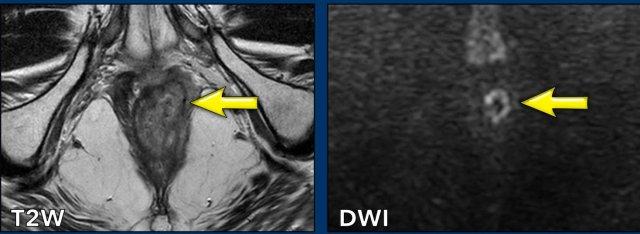

Chọn mặt phẳng đo phù hợp

Lưu ý rằng để xác định giai đoạn T, cần đo đường kính dài nhất có thể của khối u.

Để thực hiện điều này, hãy đánh giá khối u trên nhiều mặt phẳng và tìm kích thước lớn nhất của khối u.

Hình ảnh

Trong ví dụ này, đo khối u trên mặt phẳng axial có thể dẫn đến nhận định sai là khối u T1.

Khi đo trục dài nhất của khối u trên mặt phẳng coronal, giai đoạn khối u là T2.